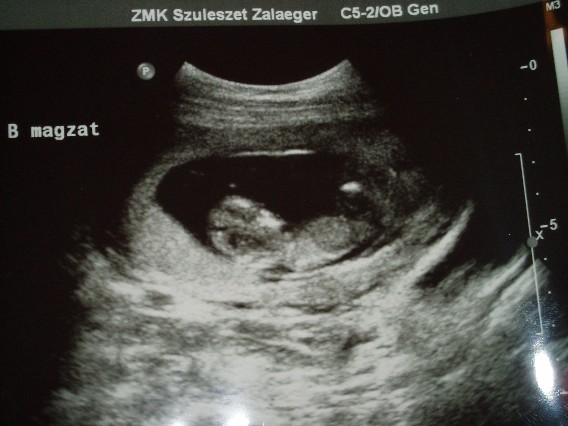

Voltunk az új drbácsinál és nagyon kedves, szimaptikus volt és minden rendben a Babákkal, megcsinálta a 12. heti genetikai uhut.

Kaptunk most olyan képet, amin együtt vannak. Ja és azt játszották, hogy lecsúsztak a zsákban, majd lábbal visszarúgták magukat és újra... írtó édesek voltak.

Minden rendben van velük, 2 nappal nagyobbnak mérte őket a gép.